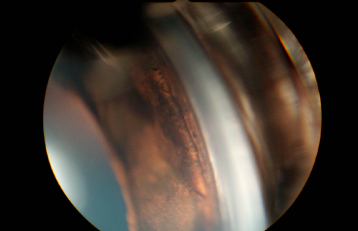

隅角鏡

05.隅角鏡